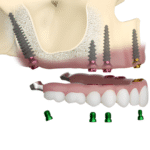

A dental implant is an artificial tooth root placed inside the jawbone to support a replacement tooth. It is usually made from titanium, a strong and body-friendly metal. After placement, the implant slowly joins with the jawbone and becomes very stable. A crown (artificial tooth) is fixed on top, giving a natural look and strong bite.

Implant has three simple parts:

Implant Screw – Placed inside the jawbone and acts like a tooth root.

Abutment – Connects the implant to the artificial tooth.

Crown –The visible tooth that matches your natural teeth in color and shape. When placed by an experienced implantologist, implants stay strong and comfortable for many years.